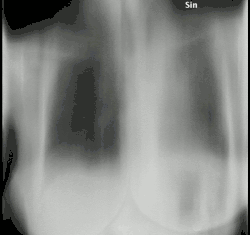

Tomosynthesis, also digital tomosynthesis (DTS), is a method for performing high-resolution limited-angle tomography at radiation dose levels comparable with projectional radiography. It has been studied for a variety of clinical applications, including vascular imaging, dental imaging, orthopedic imaging, mammographic imaging, musculoskeletal imaging, and chest imaging.[1]

Digital tomosynthesis combines digital image capture and processing with simple tube/detector motion as used in conventional computed tomography (CT). However, though there are some similarities to CT, it is a separate technique. In modern (helical) CT, the source/detector makes at least a complete 180-degree rotation about the subject obtaining a complete set of data from which images may be reconstructed. Digital tomosynthesis, on the other hand, only uses a limited rotation angle (e.g., 15-60 degrees) with a lower number of discrete exposures (e.g., 7-51) than CT. This incomplete set of projections is digitally processed to yield images similar to conventional tomography with a limited depth of field. Because the image processing is digital, a series of slices at different depths and with different thicknesses can be reconstructed from the same acquisition. However, since fewer projections are needed than CT to perform the reconstruction, radiation exposure and cost are both reduced.[4]

Chest